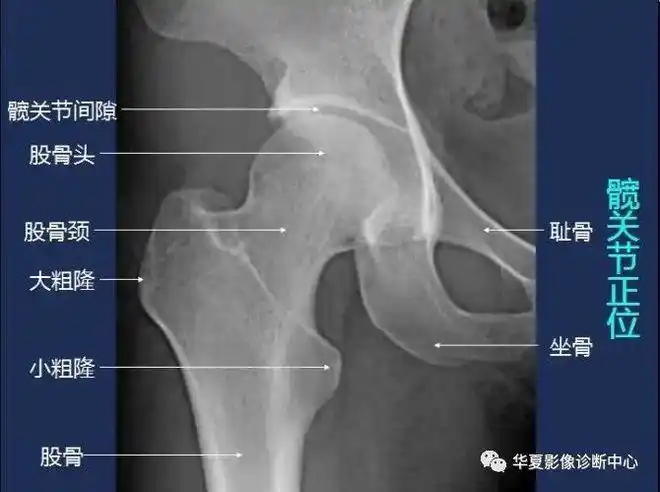

全身常规x线,骨关节mri断层解剖大全|髋关节|横断面|颈段|腰段|冠状面